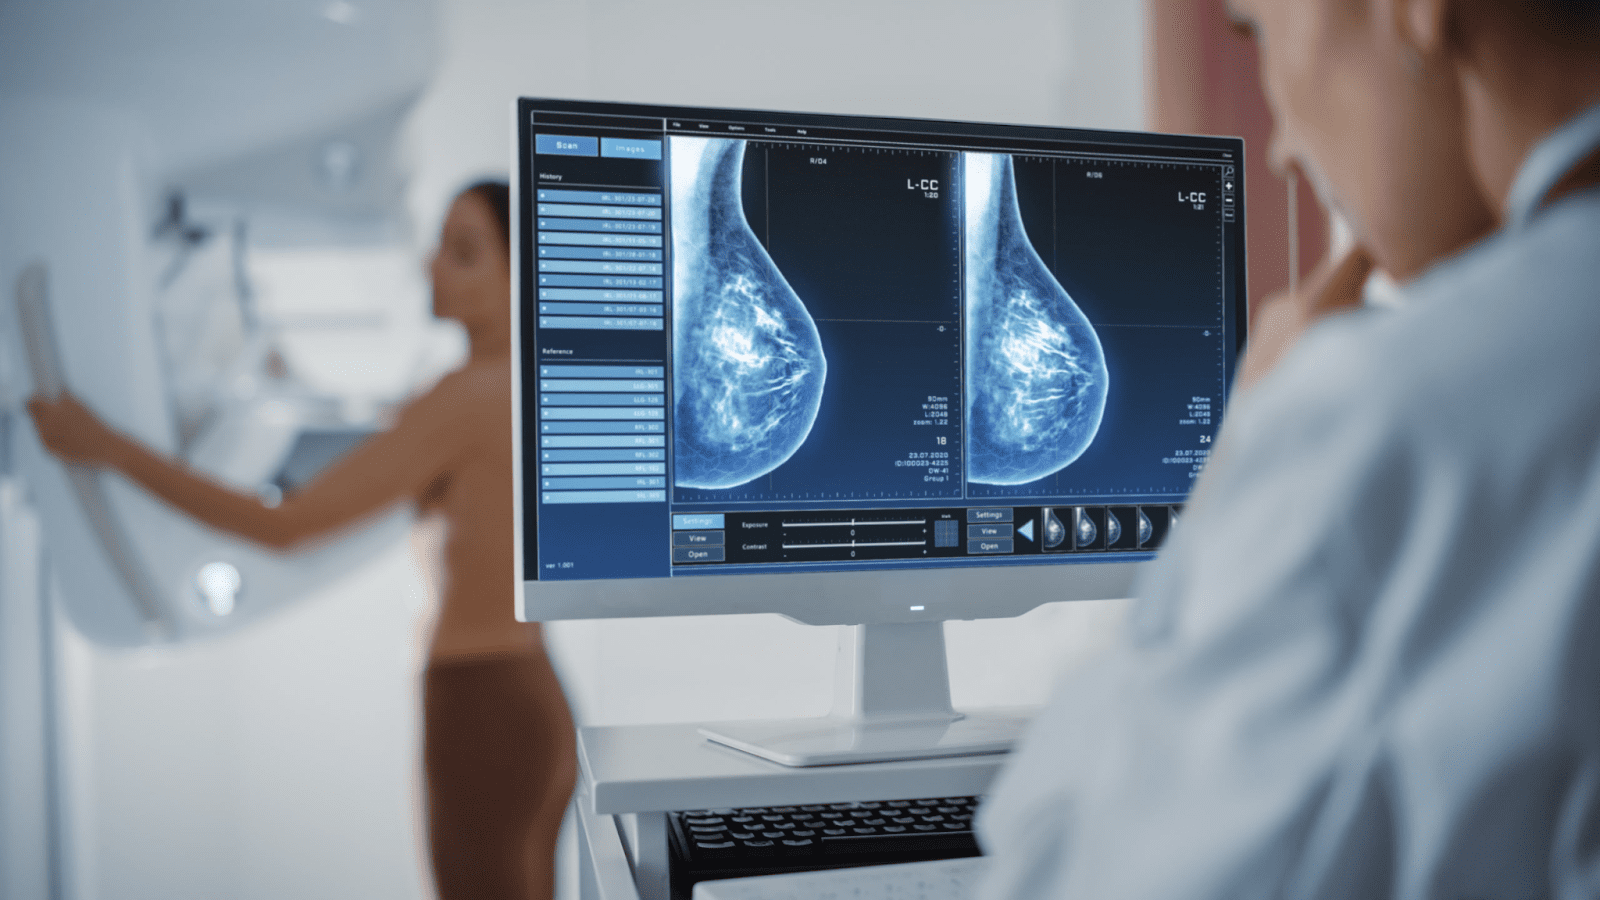

Процесс маммографии в центре проходит очень комфортно. Когда вы придете на приём, вас попросят переодеться в халат. Чтобы получить четкое изображение, технолог разместит вашу грудь на компрессионную пластину, а аппарат постепенно сжимает грудь между двумя пластинами. Это может привести к небольшой дискомфорт, но это важно для четкого изображения. Если у вас очень чувствительная грудь, рекомендуется приходить по меньшей мере за неделю до менструации.

Дискомфорт исчезнет сразу после завершения процедуры. После того, как процедура завершится, полный отчет будет направлен врачу, который вас направил на обследование.

Пациенты, имеющие сахарный диабет и использующие устройство для мониторинга уровня глюкозы, должны снять устройство, чтобы предотвратить воздействие радиации.